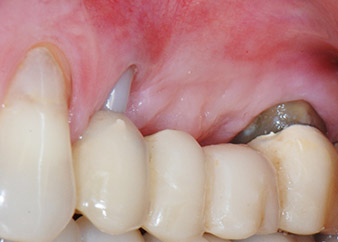

58-годишна пациентка се оплаква от болка и повишена подвижност в нейния мост върху зъб 24 с функция на абатмънт. На лице е периодонтално възпаление с дълбочина на джоба 7 mm мезиобукално и повече от 12 mm дистално, както и включена 3 градусова фуркация. Освен това, рентгенографията показва обширна периодонтална лезия около апикалната зона на (друго място) предварително ендодонтски обработен зъб 24 (Фиг. 1).

Една година по-късно, зъби 25 и 26 са екстрахирани в следствие на травма и поради ендо-перио причини, преди поставянето на моста. Комбинирана ендо-перио лезия е диагностицирана за зъб 24 от неясна етиология. Пациентката иска да задържи нейния мост с абатмънт на зъби 24 и 27 и не приема окончателна, подвижна протеза. По този начин, взаимно решихме да положим всички усилия да запазим и двата зъба, въпреки лошата прогноза за тях, която е базирана на рентгенографски и клинични резултати.

Поставянето на два импланта е планирано на места 25 и 26, в хирургична сесия с отворено периодонтално отстраняване и апикоектомия на зъб 24. В следствие на вертикален дефицит на кост в бъдещото имплантно ложе, планирана е вътрешна аугментация на синус.

След един месец, в деня на операцията, болката и възпалението в зъб 24 е минимално, но подвижността в Miller class 2 е на лице. След отваряне на ламбата и почистването на периапикалната и перирадикуларната тъкани, обхватът на костния дефект стана очевиден (Фиг. 2 и 3).

В букалния корен, цялата вестибуларна и дистална кост липсва. Захващането е значително ограничено до палатиналния корен, подчертавайки предварително лошата прогноза. Зъб 27 също откри намалено хоризонтално захващане и минимално апикално разреждане (Фиг. 1) без клинични симптоми.

Фиг. 2 и 3: След повдигане на ламбото, един месец след ендодонтския преглед и прилагане на цялостна периодонтална терапия в цялата уста, букалният корен на зъб 24 разкри тотална загуба на кост и захват.